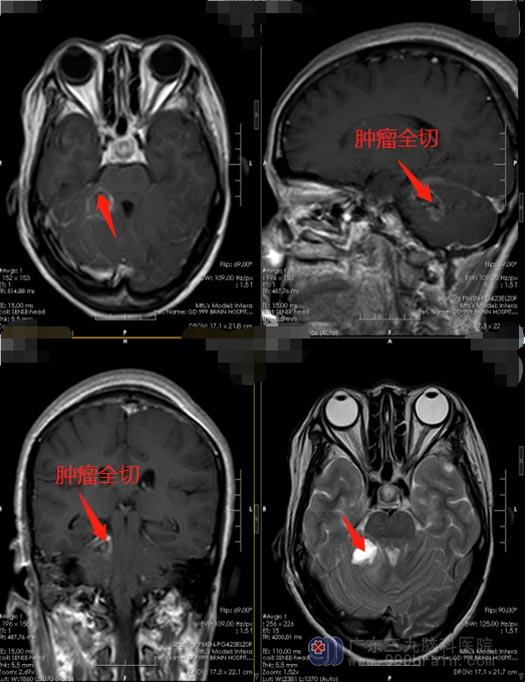

完善相关检查后,鲁明带领团队为李姐施行了“右侧小脑半球血管母细胞瘤切除术”。在神经导航、电生理监测下准确定位,避开重要的脑功能区,将肿瘤全切。

术后,李姐生命体征平稳,神志清醒,四肢活动自如,对答清晰。无癫痫发作。术后病理证实为血管母细胞瘤,李姐悬着的心总算是放了下来。